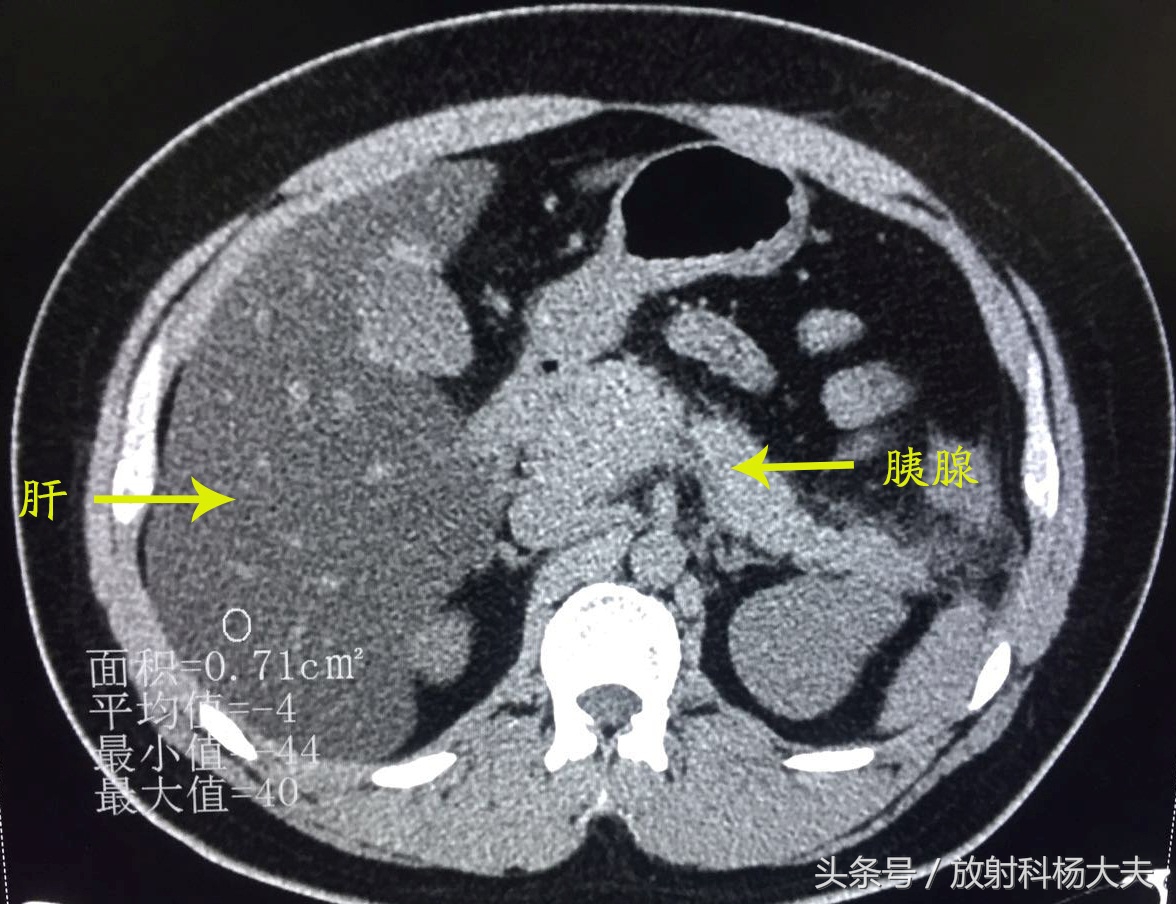

放射科的急诊总是会遇见各种急患,外伤的、头晕头痛的、恶心呕吐的、腹痛难耐的...前几天夜班来了一位身材略胖的小伙子,29岁,由于跟朋友进食火锅后突发上腹疼痛就诊,左上腹为著,为持续性胀痛,疼痛不可耐受,并向后背部放射,无肩部放射痛,疼痛不因体位变化而缓解,伴寒战、发热、大汗。做了CT,其图像如下所示:

可发现肝脏密度明显弥漫性减低,且明显低于同层面脾脏密度。胰腺周围可见渗出改变。腹痛原因找到了----急性胰腺炎伴重度脂肪肝,可这肝脏密度也太低了。

CT图像可见肝脏密度弥漫性减低,明显低于同层面脾脏密度,胰腺饱满,周围可见渗出样改变---急性胰腺炎伴重度脂肪肝。